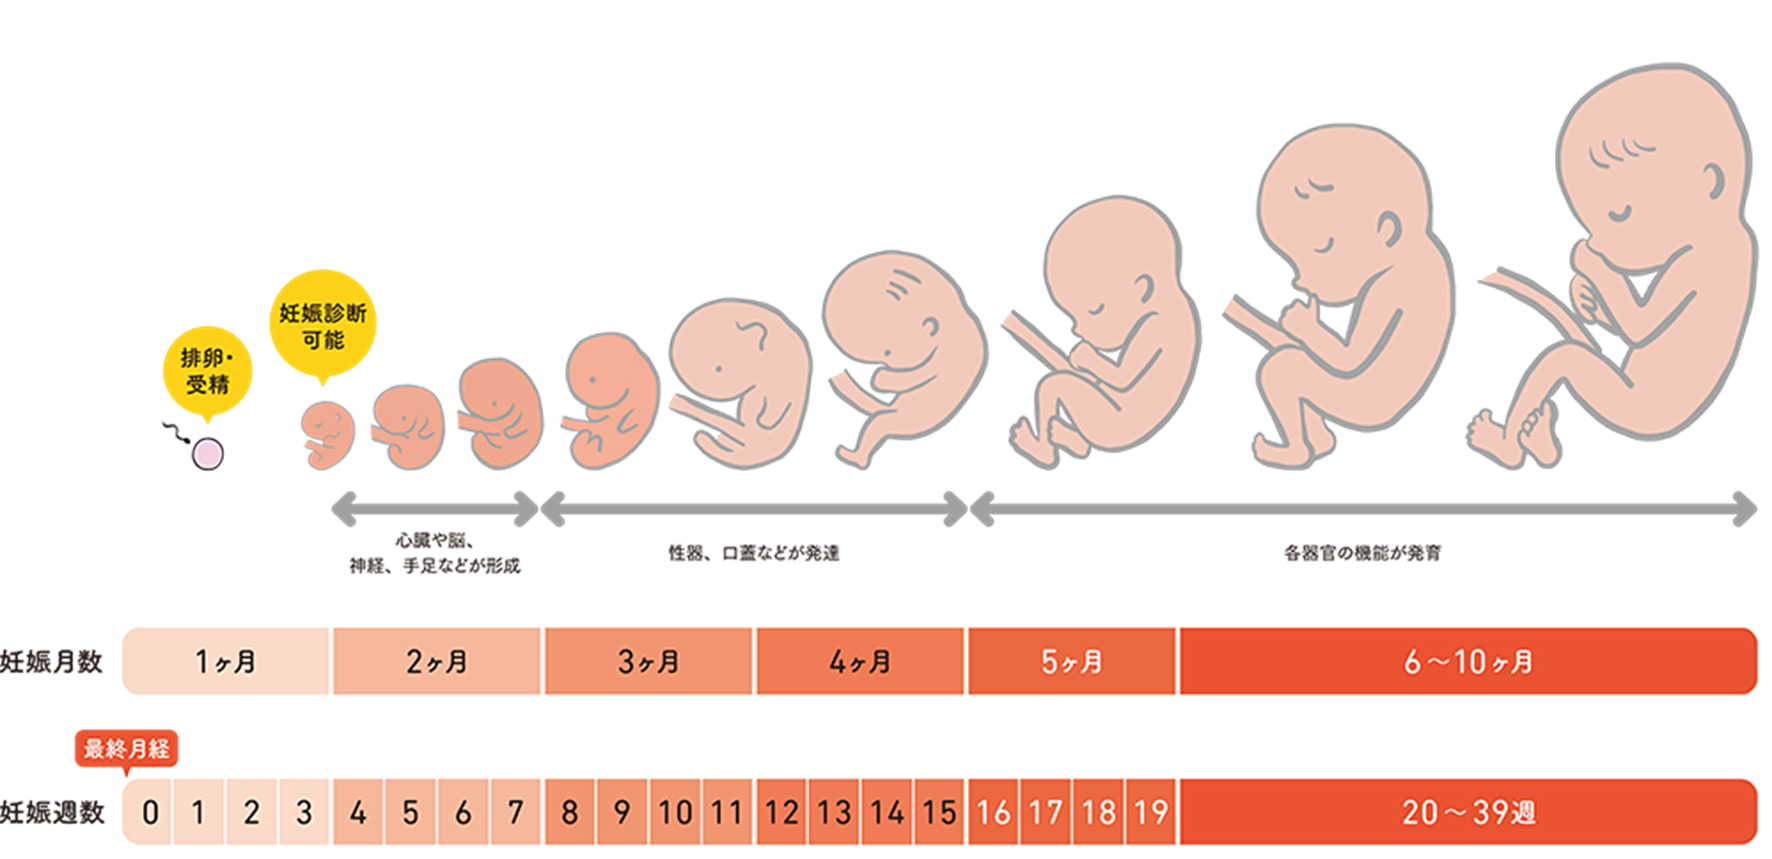

Ilustración de Stock 胎児週別成長図 3,4,5,6,7,8,9,16,20-36,38WAdobe Stock。

胎児の成長 , , ママの子宮に着床してから40週に入るまでの赤ちゃんの成長👶,お腹の中でこんなに成長してくれるので、ママのお腹はパツパツ💦🤰, ,お腹が圧迫されて息苦しかったり、気持ち悪かったり、便秘や頻尿になったり とママの身体は悲鳴をあげつつも子宮は立派に赤ちゃんを育ててくれます👏👏👏,, 出産されたママ、赤ちゃんを大切に育ててくれてくれてありがとう❣️,。

4週から40週までの胎児の成長Premiumベクトル素材。

胎児の成長過程と週数のイラスト素材103469027- PIXTA。

胎児の成長過程 妊娠初期・中期・後期の変化 FMF胎児クリニック東京ベイ幕張東京都・千葉県。